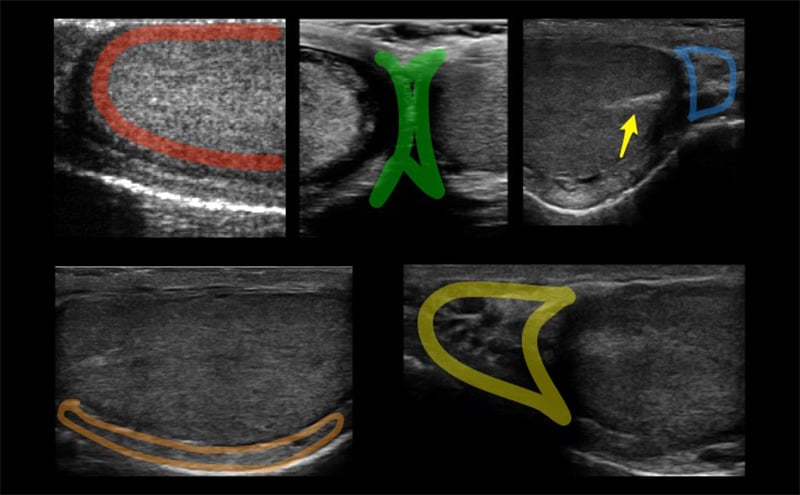

- The normal testis has midgray or medium-level echoes and is homogeneous in appearance. (Figure 3)

Figure 3. Red: Image of the normal testicle with homogenous echotexture. Green: Median raphe. Blue: Tail of the epididymis. Orange: Body of the epididymis. Yellow: Head of the epididymis. Arrow: Mediastinum testis seen as a linear echogenic band

- The epididymis has similar or slightly increased echogenicity as compared to the normal testis.

- The mediastinum testis is seen as a linear echogenic band running parallel to the epididymis, best seen on sagittal view.

- The appendix testis and appendix epididymis are small ovoid hyperechoic protuberances found at the superior pole of the testis, normally hidden by the epididymal head. Unless outlined by fluid from a hydrocele, they are difficult to find on ultrasound.